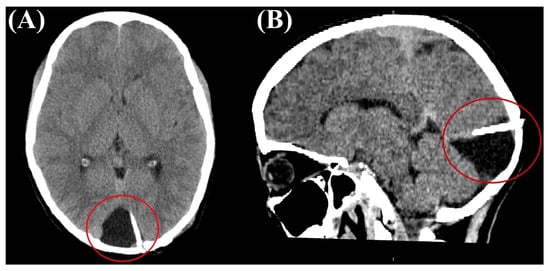

Reversible Cortical Visual Impairment in an Adolescent Due to a Posterior Fossa Arachnoid Cyst: A Case Report

2. Case Report